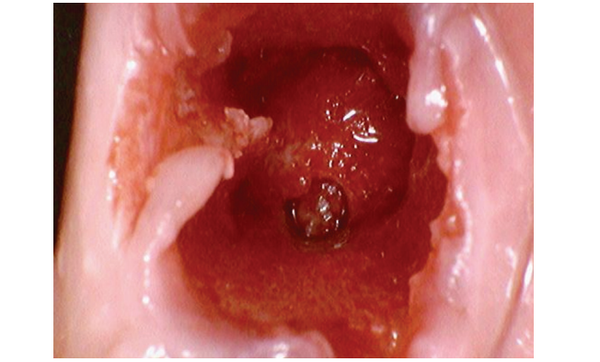

23세 남성 환자가 37번의 극심한 통증으로 내원했다. 해당 치아의 발치가 필요했으나 mandibular canal까지 거리가 3mm 정도로 가까워 safety margin을 확보하기가 어려운 상황이었다. [그림 1]

37번 발치 후 발치와에서 근심측에 식립구를 1~2mm 정도 형성했다. [그림 3]